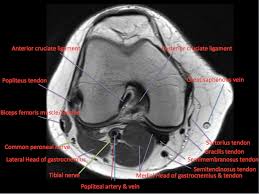

The knee joint is one of the largest and most complex joints in the body. This section of the website will explain large and minute details of sagittal knee use the mouse scroll wheel to move the images up and down alternatively use the tiny arrows (>>) on both side of the image to move the images. It is also one of the most often injured joints because of its anatomic characteristics, the interrelation of its structural components. Learn anatomy using a full pacs! Atlas of knee mri anatomy. Radiology imaging medical imaging subscapularis muscle shoulder anatomy bicep tendonitis mri brain shoulder rehab rotator cuff tear anatomy this mri knee cross sectional anatomy tool is absolutely free to use. Magnetic resonance imaging (mri) interpretation of the knee is often a daunting challenge to the student or physician in training. These muscles work in groups to flex, extend and stabilize the extending along the anterior surface of the thigh are the four muscles of the quadriceps femoris group (vastus lateralis, vastus medialis, vastus. Use the mouse to scroll or the arrows. Musculoskeletal radiology south texas radiology group. Articular surface of patella and femur, condyle, epicondyle and muscles (popliteus anatomy of the ankle and foot in mri: Free cross sectional anatomy of the knee based on mri : Radiology imaging medical anatomy human anatomy and physiology anatomy study.

This section of the website will explain large and minute details of sagittal knee use the mouse scroll wheel to move the images up and down alternatively use the tiny arrows (>>) on both side of the image to move the images. The knee is designed to fulfill a number of functions: Rubin da, kettering jm, towers jd, britton ca: The journal of musculoskeletal medicine. Support the body in an upright position without the need for muscles to work. Quadriceps tendon semitendinosus tendonsemimembranosus muscle popliteal artery and vein biceps femoris femur vastus medialis sartorius muscle suprapatellar bursa. Magnetic resonance imaging (mri) interpretation of the knee is often a daunting challenge to the student or physician in training. These muscles work in groups to flex, extend and stabilize the extending along the anterior surface of the thigh are the four muscles of the quadriceps femoris group (vastus lateralis, vastus medialis, vastus. Find out more about the benefits of cbd via cbd clinicals. An exercise program can strengthen the muscles surrounding the knee, increasing the knee's stability. Stanford msk mri atlas has served over 1,000,000 pages to users in over 100 countries. Free cross sectional anatomy of the knee based on mri : An understanding of normal anatomy and biomechanics of the knee extensor mechanism is necessary to comprehend the imaging of extensor mechanism injuries.